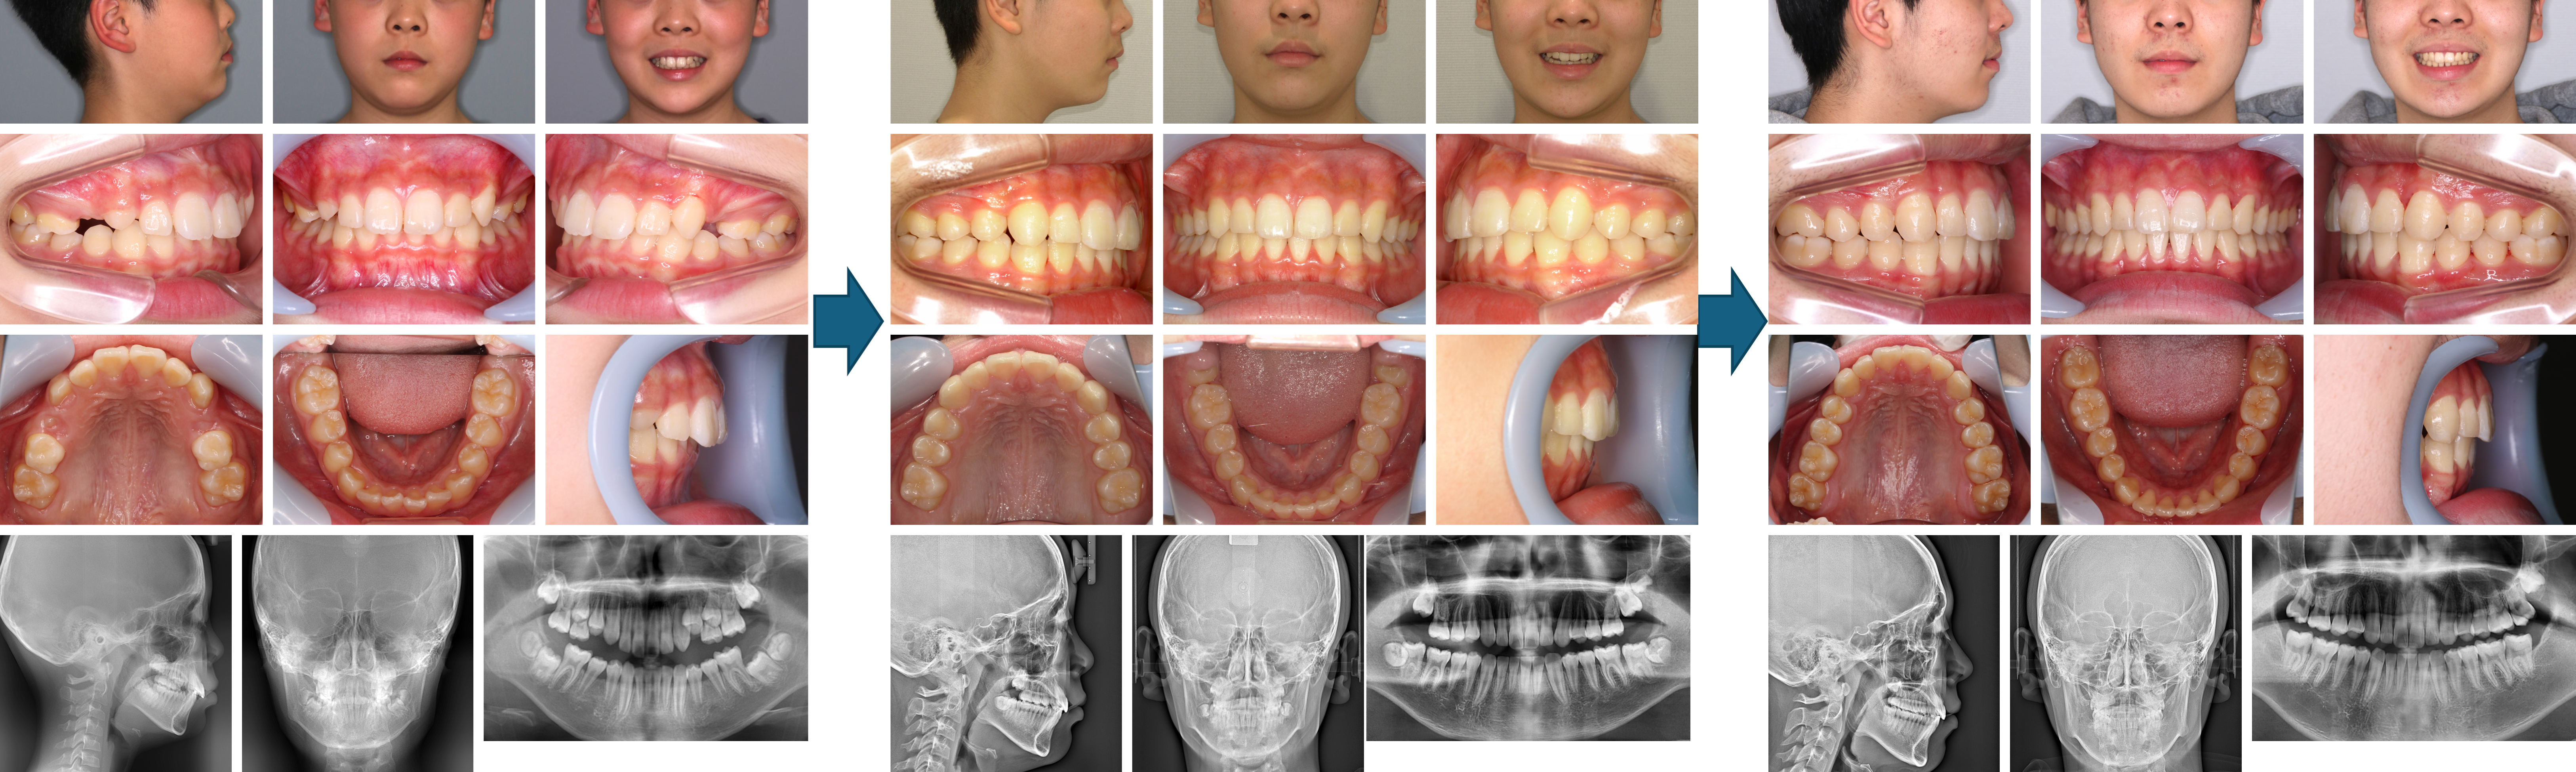

【治療例 K6925】初診時年齢:7歳9か月 / 性別:男性 / 主訴:歯が生えかわってきて歯並びが気になりだした

治療の概要:本症例は歯の生えかわりに伴い歯並びと睡眠時の歯ぎしりを主訴に来院された。過蓋咬合のほか、パノラマエックス線写真より上顎左側第一小臼歯の萌出空隙の不足が認められた。上顎両側第一大臼歯の遠心移動を行い小臼歯の萌出スペースの獲得ならびに上顎前歯の後退を行った。一旦は、上下顎の第一大臼歯まで緊密な咬合を獲得することが出来たが、第二大臼歯が萌出してきたころには上顎右側第二大臼歯の鋏状咬合が認められたため、下顎第三大臼歯を抜去後に追加アライナーにて上下顎第二大臼歯の咬合を完成させた症例である。

主訴:歯が生えかわってきて歯並びが気になりだした

診断名:上下前歯部の過蓋咬合症例

使用した主な装置:アライナー型(マウスピース型)矯正装置(インビザライン®)、IPR

抜歯/非抜歯および抜歯部位:非抜歯(ただし、乳歯の抜歯はあり)

治療期間:4年7か月

治療回数:37回

アライナー枚数:初回41枚(37枚で中止)+追加①20枚+追加②21枚 合計78枚